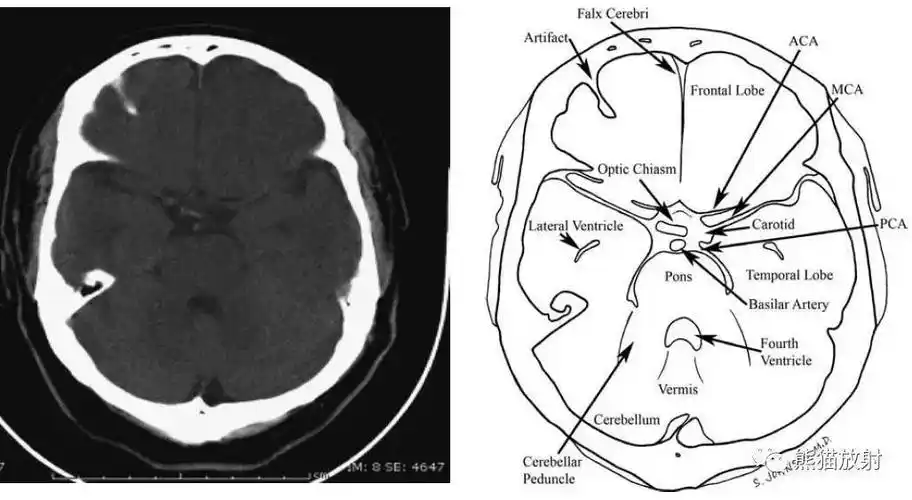

从前至后:额窦,鸡冠,蝶鞍,脑桥,小脑脚,小脑,四脑室.